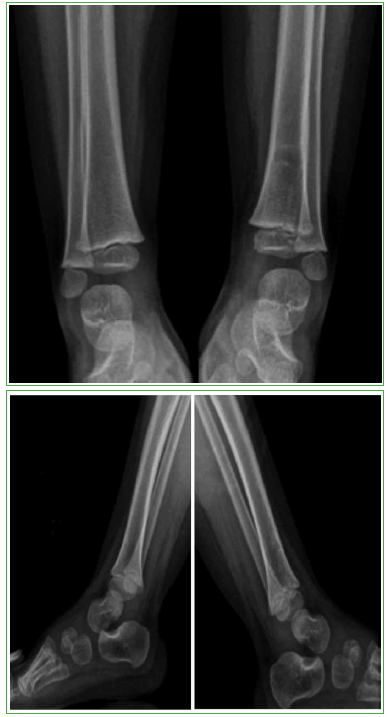

La evolución de la paciente fue muy favorable, sin dolor, ni secuelas motoras, ni daño esquelético residual, sin compromiso de la fisis, ni del crecimiento del miembro. Se puede observar la evolución de la lesión ósea en los controles radiográficos posoperatorios (Figuras 3-5).

Figura 3.

Radiografías de frente y de perfil, de ambos tobillos, al año de la intervención.

Figura 4.

Radiografías de frente y de perfil, de ambos tobillos, a los dos años de la intervención.